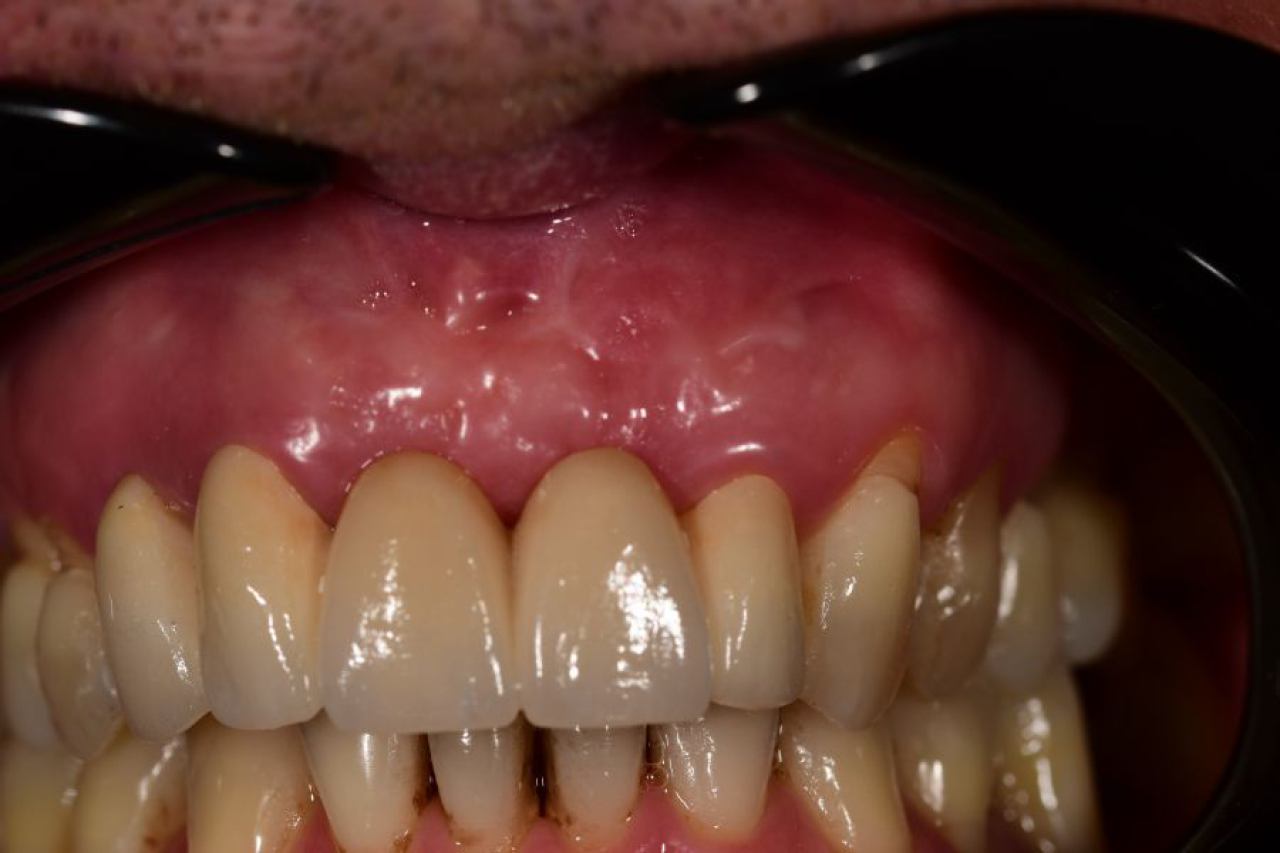

Parodontologija i kirurgija

Parodontologija je grana dentalne medicine koja se bavi zdravljem potpornih struktura zuba (parodonta). Parodont se sastoji od zubnog mesa (gingiva), kosti i vlakana koja vežu zub za kost (parodontalni ligament).

Ovo je grana kojoj Marković Dental Clinic pridaje puno pažnje jer je vrlo kompleksna i bitna za cijelo oralno zdravlje.

Regeneracija kosti i mekog tkiva

Gingivalne recesije u narodu poznatije kao „povlačenje zubnog mesa" moguće je korigirati kirurškim zahvatom te vratiti gingivu (zubno meso) u fiziološki položaj mikrokirurškim tehnikama. Zahvati koje odrađujemo kod regeneracije kosti i mekog tkiva su podizanje dna sinusa (sinus lift) i nadomještanje izgubljenog volumena kosti (augmentacija kosti, regeneracija kosti).